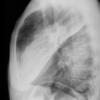

Case 3 RM & UL pneum Lat

Date: 07/04/2004

Views: 7248